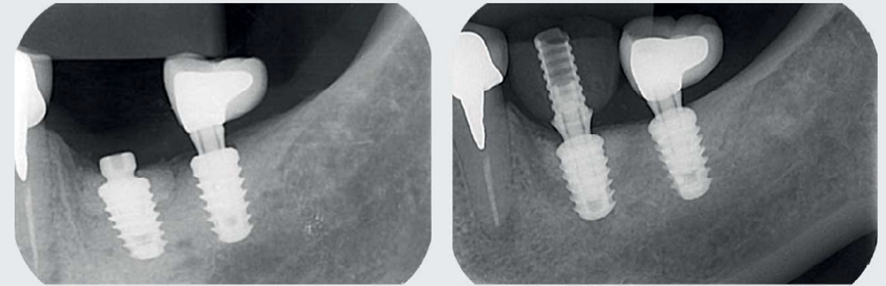

A abordagem cirúrgica proposta foi realizada com retalho total, preservando as papilas adjacentes através de incisões sobre a crista e proximais relaxantes, seguida de desbridamento com curetas metálicas periodontais convencionais e pontas ultrassônicas diamantadas piezocirúrgicas (Figura 2). Em seguida, após a instrumentação mecânica descrita, foi utilizado jato de bicarbonato de sódio + ácido fosfórico 37% (dois minutos) + EDTA 24% (dois minutos) + irrigação com solução salina para descontaminação da superfície do implante (Figura 3). Finalizada a descontaminação, foi colocado um parafuso de cobertura com 1,5 mm para permitir o fechamento primário do retalho e uma posterior reentrada sem exposição tecidual excessiva. Devido às características morfológicas intraósseas do defeito serem favoráveis à regeneração, foi realizado enxerto ósseo com substituto ósseo xenógeno Extra Graft XG-13 (75% de hidroxiapatita natural bovina + 25% de colágeno) associado ao Endogain (matriz derivada do esmalte). As excelentes propriedades hidrofílicas do Extra Graft, junto às proteínas amelogeninas do Endogain, proporcionaram um enxerto com fácil manuseio e propriedades osteocondutivas. Além disso, podem melhorar o potencial biológico para neoformação óssea em um ambiente fisicamente estável e protegido pela membrana de colágeno. Após o completo preenchimento até o nível vertical dos limites circunferenciais, o enxerto foi coberto com uma membrana de colágeno natural bovino (Figura 4).

Após quatro meses, foi realizada uma reabertura minimamente invasiva para colocação de provisório (Figura 5) e, somente após cinco meses, foi concluída a coroa (Figura 6).